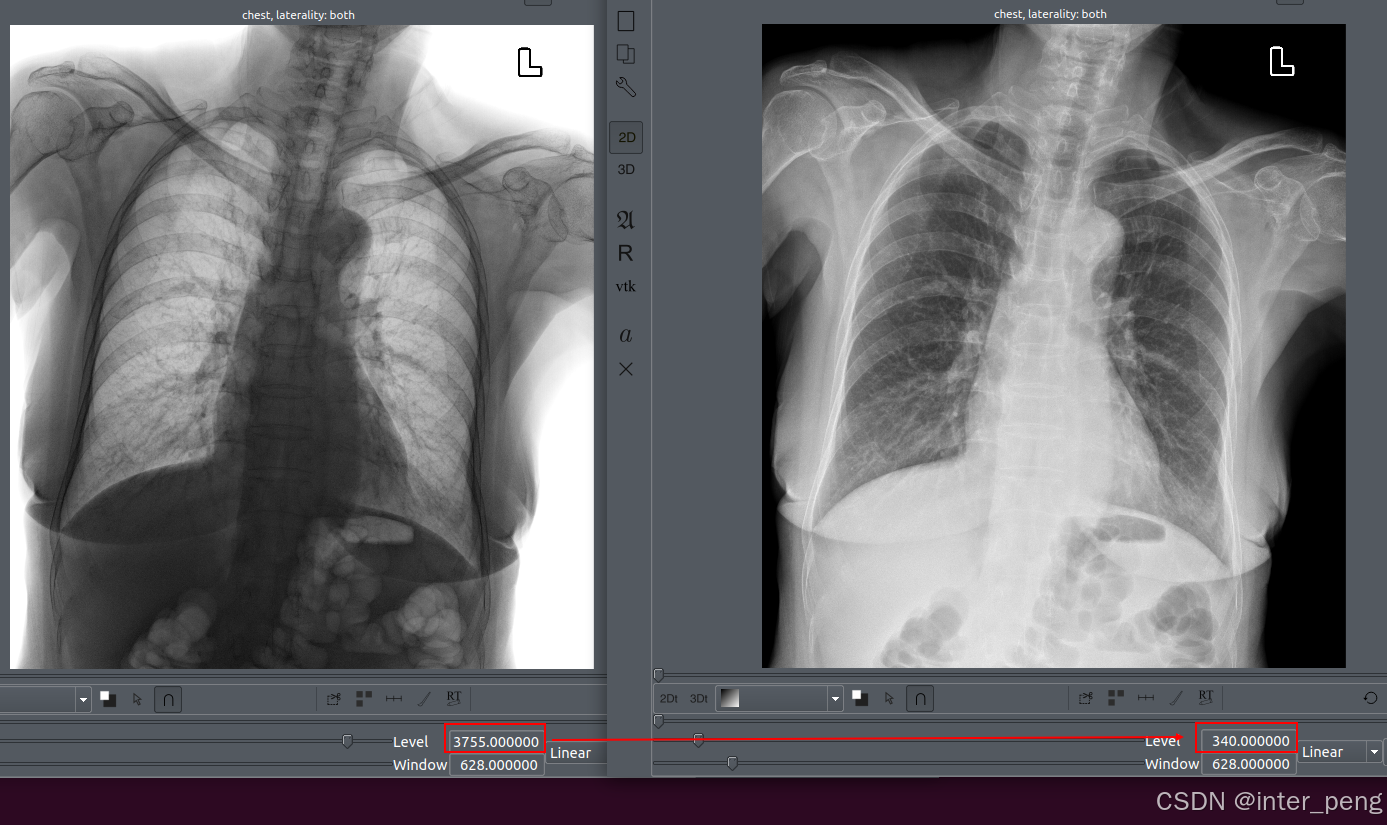

以上是增加了, 修改窗位后的, 反色前后的图像对比.

可以看到, 两幅图像的窗位发生了变化. 反片是3755, 正片是340.